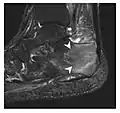

Fatigue fractures are more frequent in women which may be due to the relatively smaller bones of women. Moreover, pregnancy is a well-recognized risk factor for femoral neck fatigue fracture. While fibular and metatarsal fractures have a low risk of complications, other sites including the femoral neck, midanterior tibia, navicular, talar, and other intraarticular fractures are prone to complications such as delayed union, nonunion, and displacement. The site of the insufficiency fracture may be specific to the activity: for example, rugby and basketball players are more prone to navicular fractures, while gymnasts have a higher risk for talar fractures (Figure 7). Long distance runners are at increased risk for pelvic, tibial (Figures 8 and 9), and fibular fractures. In the military, calcaneus (Figure 10) and metatarsals are the most commonly cited injuries, especially in new recruits. Billiard players are at risk for upper limb fractures (Figure 11).[1]

Figure 10: Calcaneal fatigue fracture in a 30-year-old male runner. Radiographs were normal (not shown). (a) Sagittal T1-weighted and (b) short tau inversion recovery images show a linear hypointensity (arrows) of calcaneal tuberosity within diffuse bone marrow edema, which appears as an ill-defined area of hyperintensity on a fluid sensitive pulse sequence (arrowheads).[1]